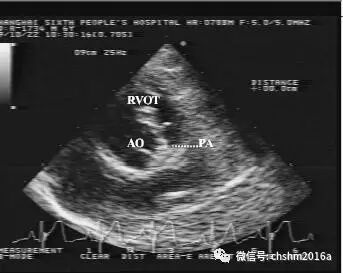

图2.3.12   显示狭窄的肺动脉主干

AO:主动脉  PA:肺动脉  RVOT:右室流出道